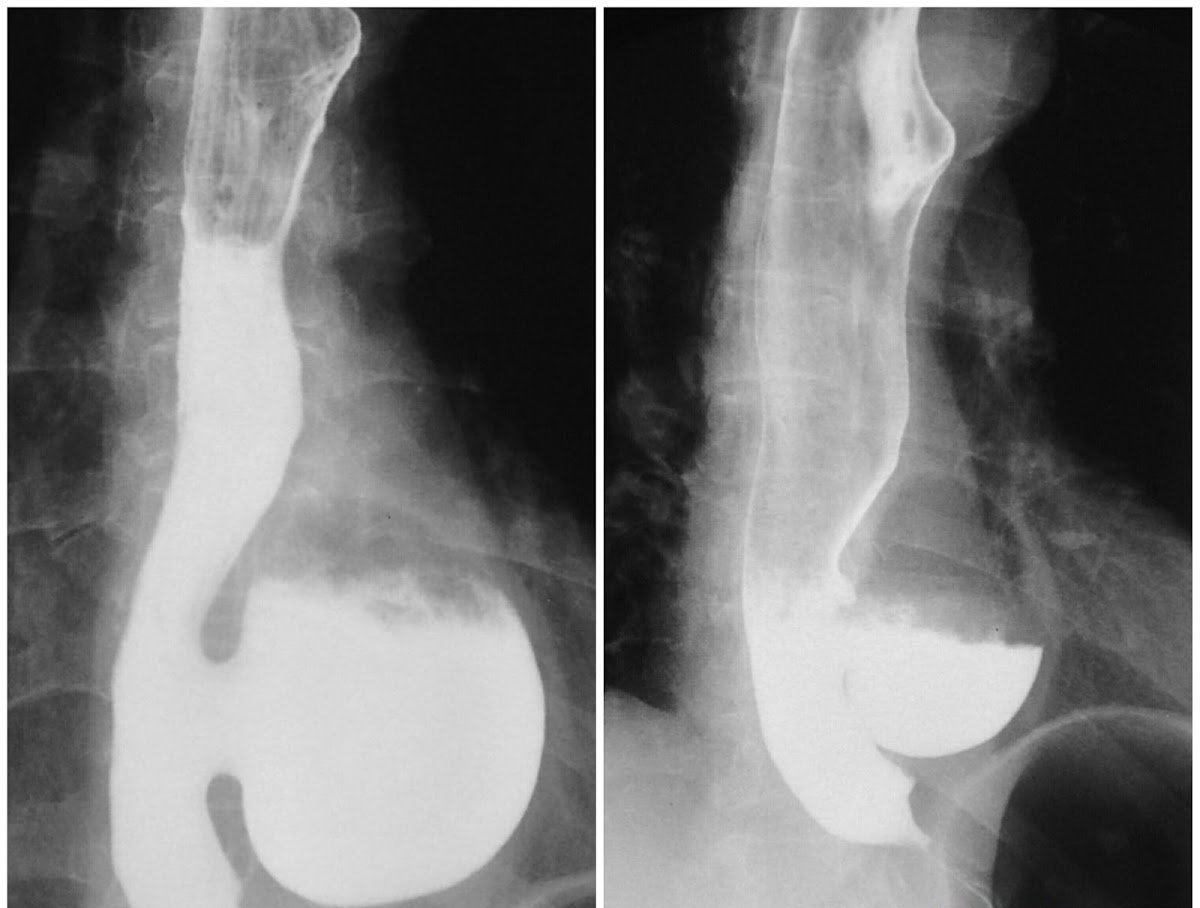

- Chụp X-quang thực quản: Kỹ thuật này sử dụng có cản quang, từ đó giúp chẩn đoán có cổ dính vào thực quản, thường nằm từ 1/3 giữa hoặc ngay phần trên của cơ hoành.